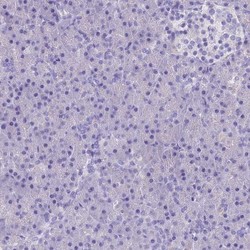

- Main image

- Experimental details

- Immunohistochemistry-Paraffin: RP5-1077B9.4 Antibody [NBP1-87394] - Staining of human liver shows moderate cytoplasmic positivity in hepatocytes.